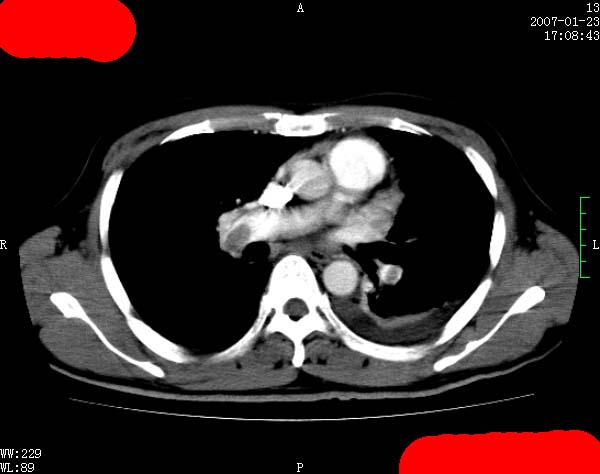

以下是引用jiangjing在2007-1-24 23:35:00的发言:[br]支持 增强扫描见右肺动脉干、左下肺动脉见充盈缺损。印象为:1、右肺动脉干、左下肺动脉栓塞。 2、左侧胸腔积液合并左肺下叶被动性肺不张。

以下是引用rjg199343在2007-1-24 23:22:00的发言:[br]增强扫描见右肺动脉干、左下肺动脉见充盈缺损。印象为:1、右肺动脉干、左下肺动脉栓塞。 2、左侧胸腔积液合并左肺下叶被动性肺不张。